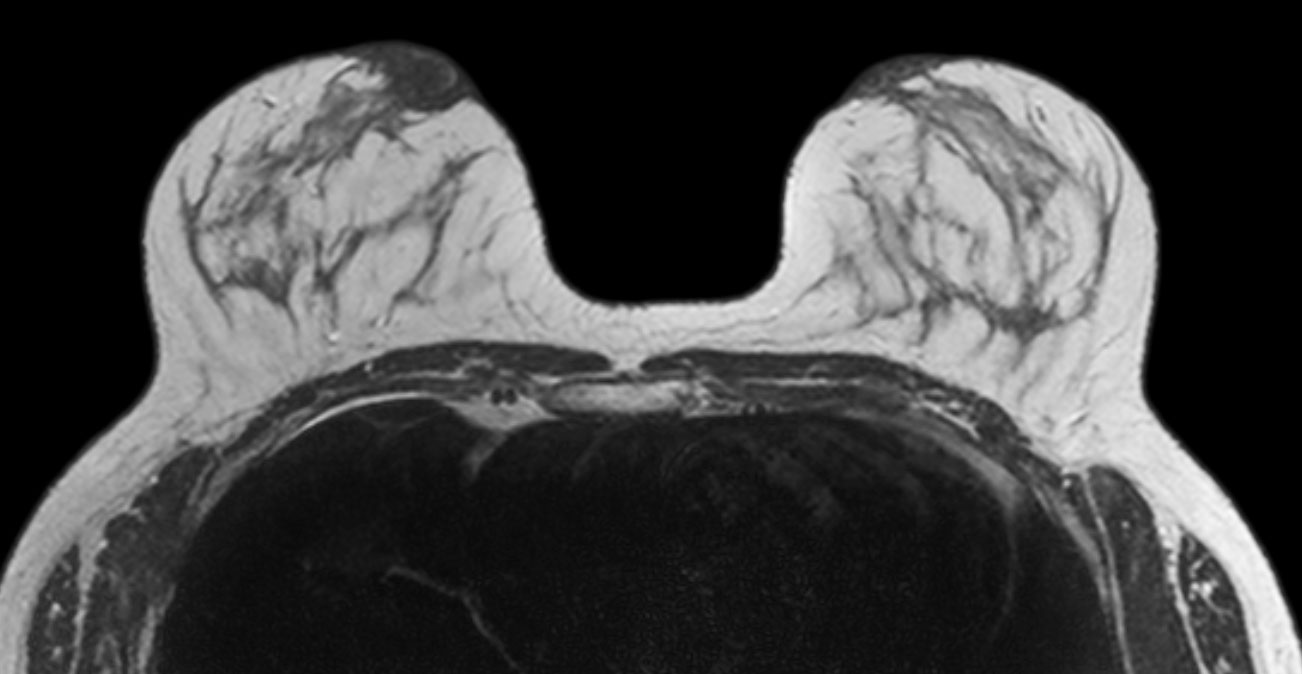

Breast imaging using SmartExam

Used Solution